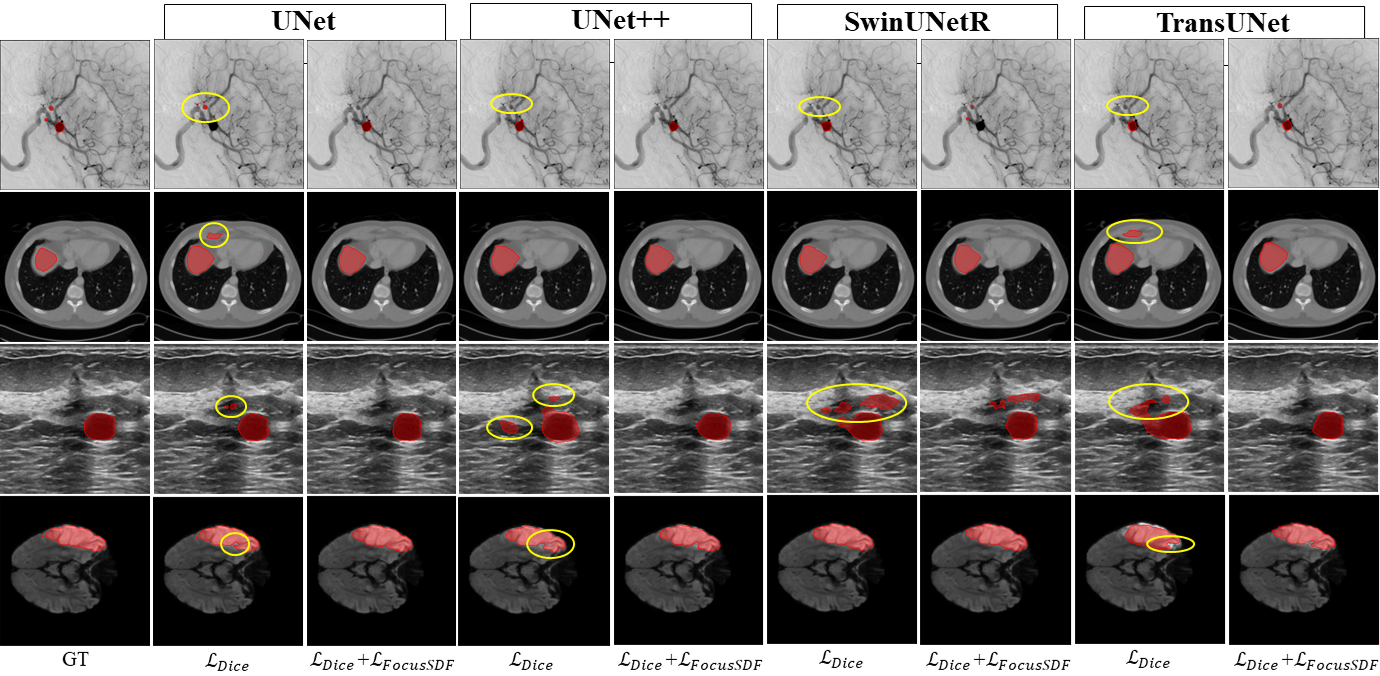

Table 2 summarizes the quantitative as well as Fig. 5presents the qualitative results of the proposed FocusSDF loss. FocusSDF achieves relatively superior overlap and boundary accuracy, especially in challenging case such as cerebral aneurysm. Its consistent performance across both CNN and transformer-based models highlights its generality and robustness in handling diverse anatomical structures and imaging modalities. Fig. 4 highlights the convergence and stability behavior of the FocusSDF on aneurysm dataset across models.

Refer to caption

Fig. 5: Qualitative comparison of segmentation outputs across datasets. Incorporating the proposed FocusSDF loss alongside the Dice loss yields superior boundary precision and structural continuity preservation compared to using the Dice loss alone. Mispredictions with dice loss are encircled as shown.